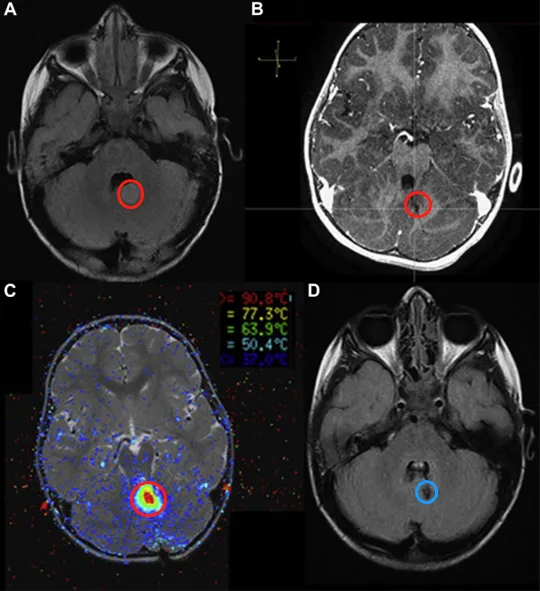

术前脑部磁共振成像MRI显示右侧丘脑增强肿瘤

术中磁共振成像MRI。(A)目标区域/位置的确认;(B)实时温度:最终图像;(C)损坏模型:2.5毫米x 9.5毫米;(D)钆消融后立即T1-MRI。

消融后3个月的磁共振成像MRI,肿瘤体积缩小了70%

患者消融前的磁共振成像(MRI)(A),使用ROSA软件与轴位T1对比后图像(B)配准的轨迹规划成像,与轴位联合配准的消融内热成像T2图像(C)和6个月消融后轴位FLAIR核磁共振成像(D)。